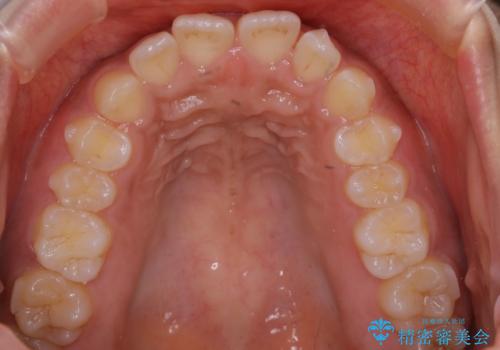

インビザライン矯正 歯を抜かずに出っ歯を改善!

- 出っ歯と前歯の隙間が空いていることを気にされて来院されました。

また、自然な感じで口元を下げていとのことでした。

奥歯のかみ合わせが問題なかったため、上顎の前歯の隙間を閉じるとともに、上顎の歯の側面を削ることをメインにして、出っ歯を改善する治療計画としました。

上顎の歯の傾きを変えるうえで、下顎の歯とのバランスのことも考え、下顎の歯の側面も削ることを加えています。

また、今回は口元を変えたい中に、劇的な変化は避けたいとのことだったので、抜歯をしない計画としています。

抜歯をしない場合、口元の変化は感じにくいですが、前歯の傾きが変わることで、口の閉じやすさは感じていただけたとのことです。

症例にもよりますが、本症例は奥歯のかみ合わせに問題がなかったので歯の側面を削ることメインに、前歯の傾きを改善することができました。

抜歯を行う場合や抜歯をしなくても奥歯の位置をずらす場合は、治療期間が長期化することが多いですが、今回は歯を削ることで改善できたため、短期間で治療を完了することができました。